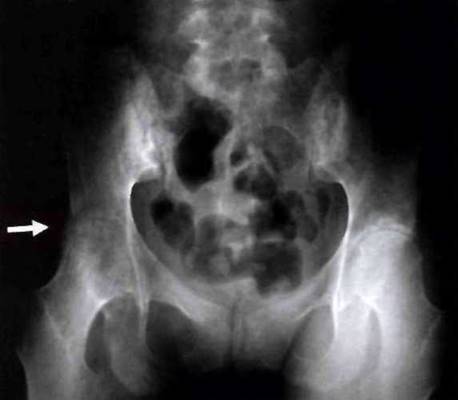

Рис. 23-20. Рентгенограмма таза больного ЮАС: сакроилеит III стадии - частичный анкилоз крестцово-подвздошных сочленений, «костные мостики» больше выражены справа.